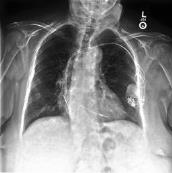

Large numbers of labeled medical images are essential for the accurate detection of anomalies, but manual annotation is labor-intensive and time-consuming. Self-supervised learning (SSL) is a training method to learn data-specific features without manual annotation. Several SSL-based models have been employed in medical image anomaly detection. These SSL methods effectively learn representations in several field-specific images, such as natural and industrial product images. However, owing to the requirement of medical expertise, typical SSL-based models are inefficient in medical image anomaly detection. We present an SSL-based model that enables anatomical structure-based unsupervised anomaly detection (UAD). The model employs the anatomy-aware pasting (AnatPaste) augmentation tool. AnatPaste employs a threshold-based lung segmentation pretext task to create anomalies in normal chest radiographs, which are used for model pretraining. These anomalies are similar to real anomalies and help the model recognize them. We evaluate our model on three opensource chest radiograph datasets. Our model exhibit area under curves (AUC) of 92.1%, 78.7%, and 81.9%, which are the highest among existing UAD models. This is the first SSL model to employ anatomical information as a pretext task. AnatPaste can be applied in various deep learning models and downstream tasks. It can be employed for other modalities by fixing appropriate segmentation. Our code is publicly available at: https://github.com/jun-sato/AnatPaste.

翻译:大量贴有标签的医学图像对于准确检测异常现象至关重要,但人工注解是劳动密集型和耗费时间的。自监学习(SSL)是一种培训方法,用于在不人工注解的情况下学习特定数据特征。一些基于SSL的模型被用于医学图像异常现象的检测。这些SSL方法有效地学习了多个特定领域图像的表解,如自然和工业产品图像。然而,由于医学专业知识的要求,基于SSL的典型模型在医学图像异常现象检测方面效率低下。我们展示了一个基于SSL的模型,可以进行基于解剖结构的、不受监督的异常现象检测(UAAD)。该模型使用解剖-觉粘贴(AnatPaste)增强工具。基于SSL的几种模型用于医学图像异常现象。这些异常现象与真正的异常相似,有助于模型识别这些异常现象。我们在三种开源的胸腔辐射数据集中可以使用模型,在基于解剖面结构结构的曲线下(AUSC),在92.1号中使用解析(Anal-SL)粘度图解为最高格式。